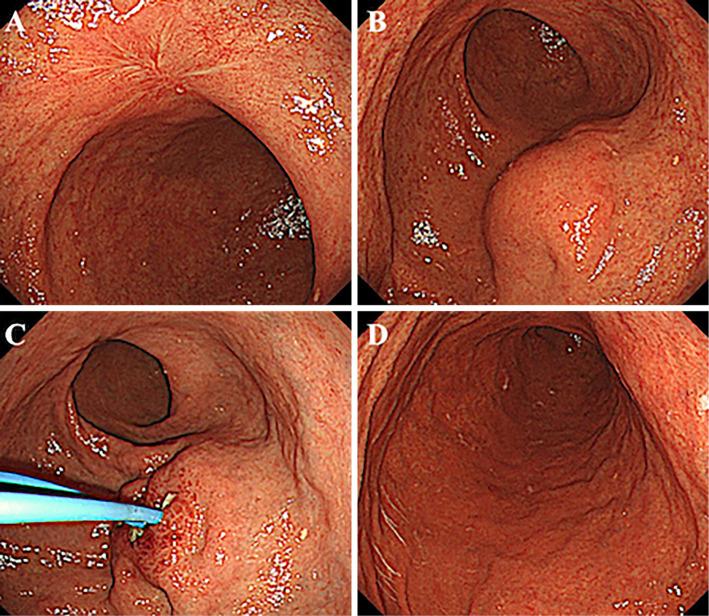

A 72-year-old man had undergone uncomplicated endoscopic submucosal dissection (ESD) with en bloc resection of a localized 20-mm IIc lesion in the anterior wall of the gastric angle. Twenty-eight days later, he was re-admitted with epigastric pain of one-week duration. Contrast-enhanced computed tomography (CT) revealed a 60-mm mass bordered by viscera; repeat endoscopy confirmed a smooth elevated submucosal tumor at the greater curvature on the oral side of the post-ESD ulcer. We diagnosed him with a perigastric abscess as a complication of ESD and performed endoscopic ultrasound-guided drainage. Subsequently, the symptoms and blood inflammatory parameters improved, and follow-up CT showed the disappearance of the abscess.

一位 72 岁男性因胃角前壁局限性 20mm IIc 病变接受了单纯内镜黏膜下剥离术(ESD)整块切除。28 天后,他因上腹痛再次入院,病程为一周。增强 CT 显示一个 60mm 大小的肿块,边界为内脏;重复内镜检查确认在 ESD 溃疡的口侧胃大弯处有一个光滑的隆起性黏膜下肿瘤。我们诊断为 ESD 术后胃周脓肿并发症,并进行了内镜超声引导下引流。随后,症状和血液炎症参数改善,随访 CT 显示脓肿消失。